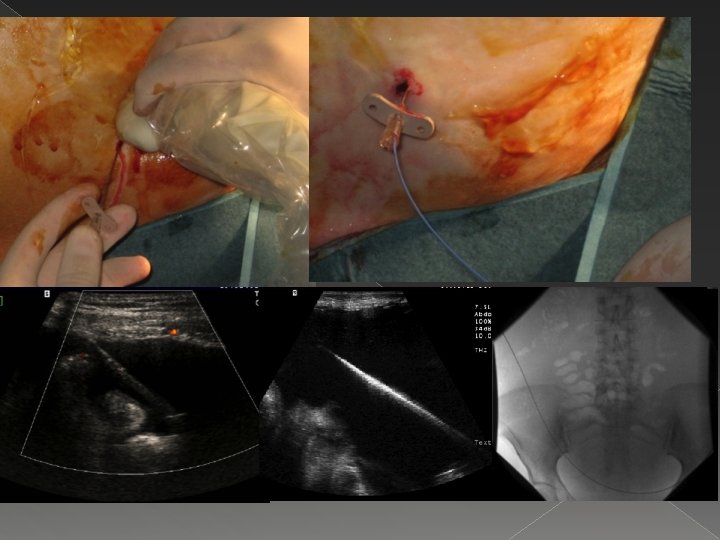

Tünelli Peritoneal Kateter � Literatüre göre 1 ay içerisinde 2 -3 defa yüksek volümlü parasentez ihtiyacı olması durumunda refrakter malign asit varlığından söz edilir. � Refrakter malign asit varlığında ilk seçenek olarak tünelli peritoneal kateter düşünülmelidir. � Kateterden kemoterapötik ajan verilebilir. � Tünel enfeksiyonu ve peritonit geç komplikasyonlardır. � İşlem sırasında 1 gr. İv sefazolin sodyum

Tünelli Peritoneal Kateter Medcomp peritoneal kateter

Tünelli Peritoneal Kateter � Tıkanma: transkateter t-PA � Malpozisyon: Floroskopi altında revizyon � Çıkma: Trakt iyileşmesini takiben yeni kateter � Basit tünel enfeksiyonu: İV antibiyotik � Ciddi tünel enfeksiyonu: kateterin çıkartılması ve antibiyotik � Peritonit: Pigtail drenaj kateteri